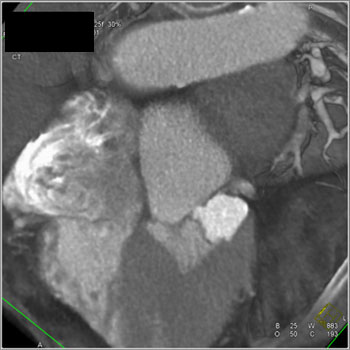

![]() | Question 3: 87 yr old female with history of hypertension had negative stress echo, presents with acute chest pain. What’s the diagnosis? |